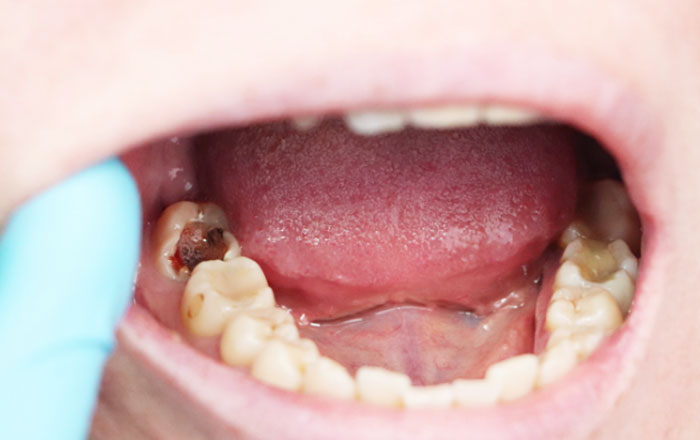

まず多いのが、虫歯が歯茎の下まで深く入り込んでいる状態です。歯の見えている部分(歯冠)が大きく崩れ、土台となる歯質がほとんど残っていないこともあります。

- 被せ物が外れたら内部が大きく崩れていた

- 差し歯の中で虫歯が進行していた

- 神経を取った歯が長年の負担で割れかけている